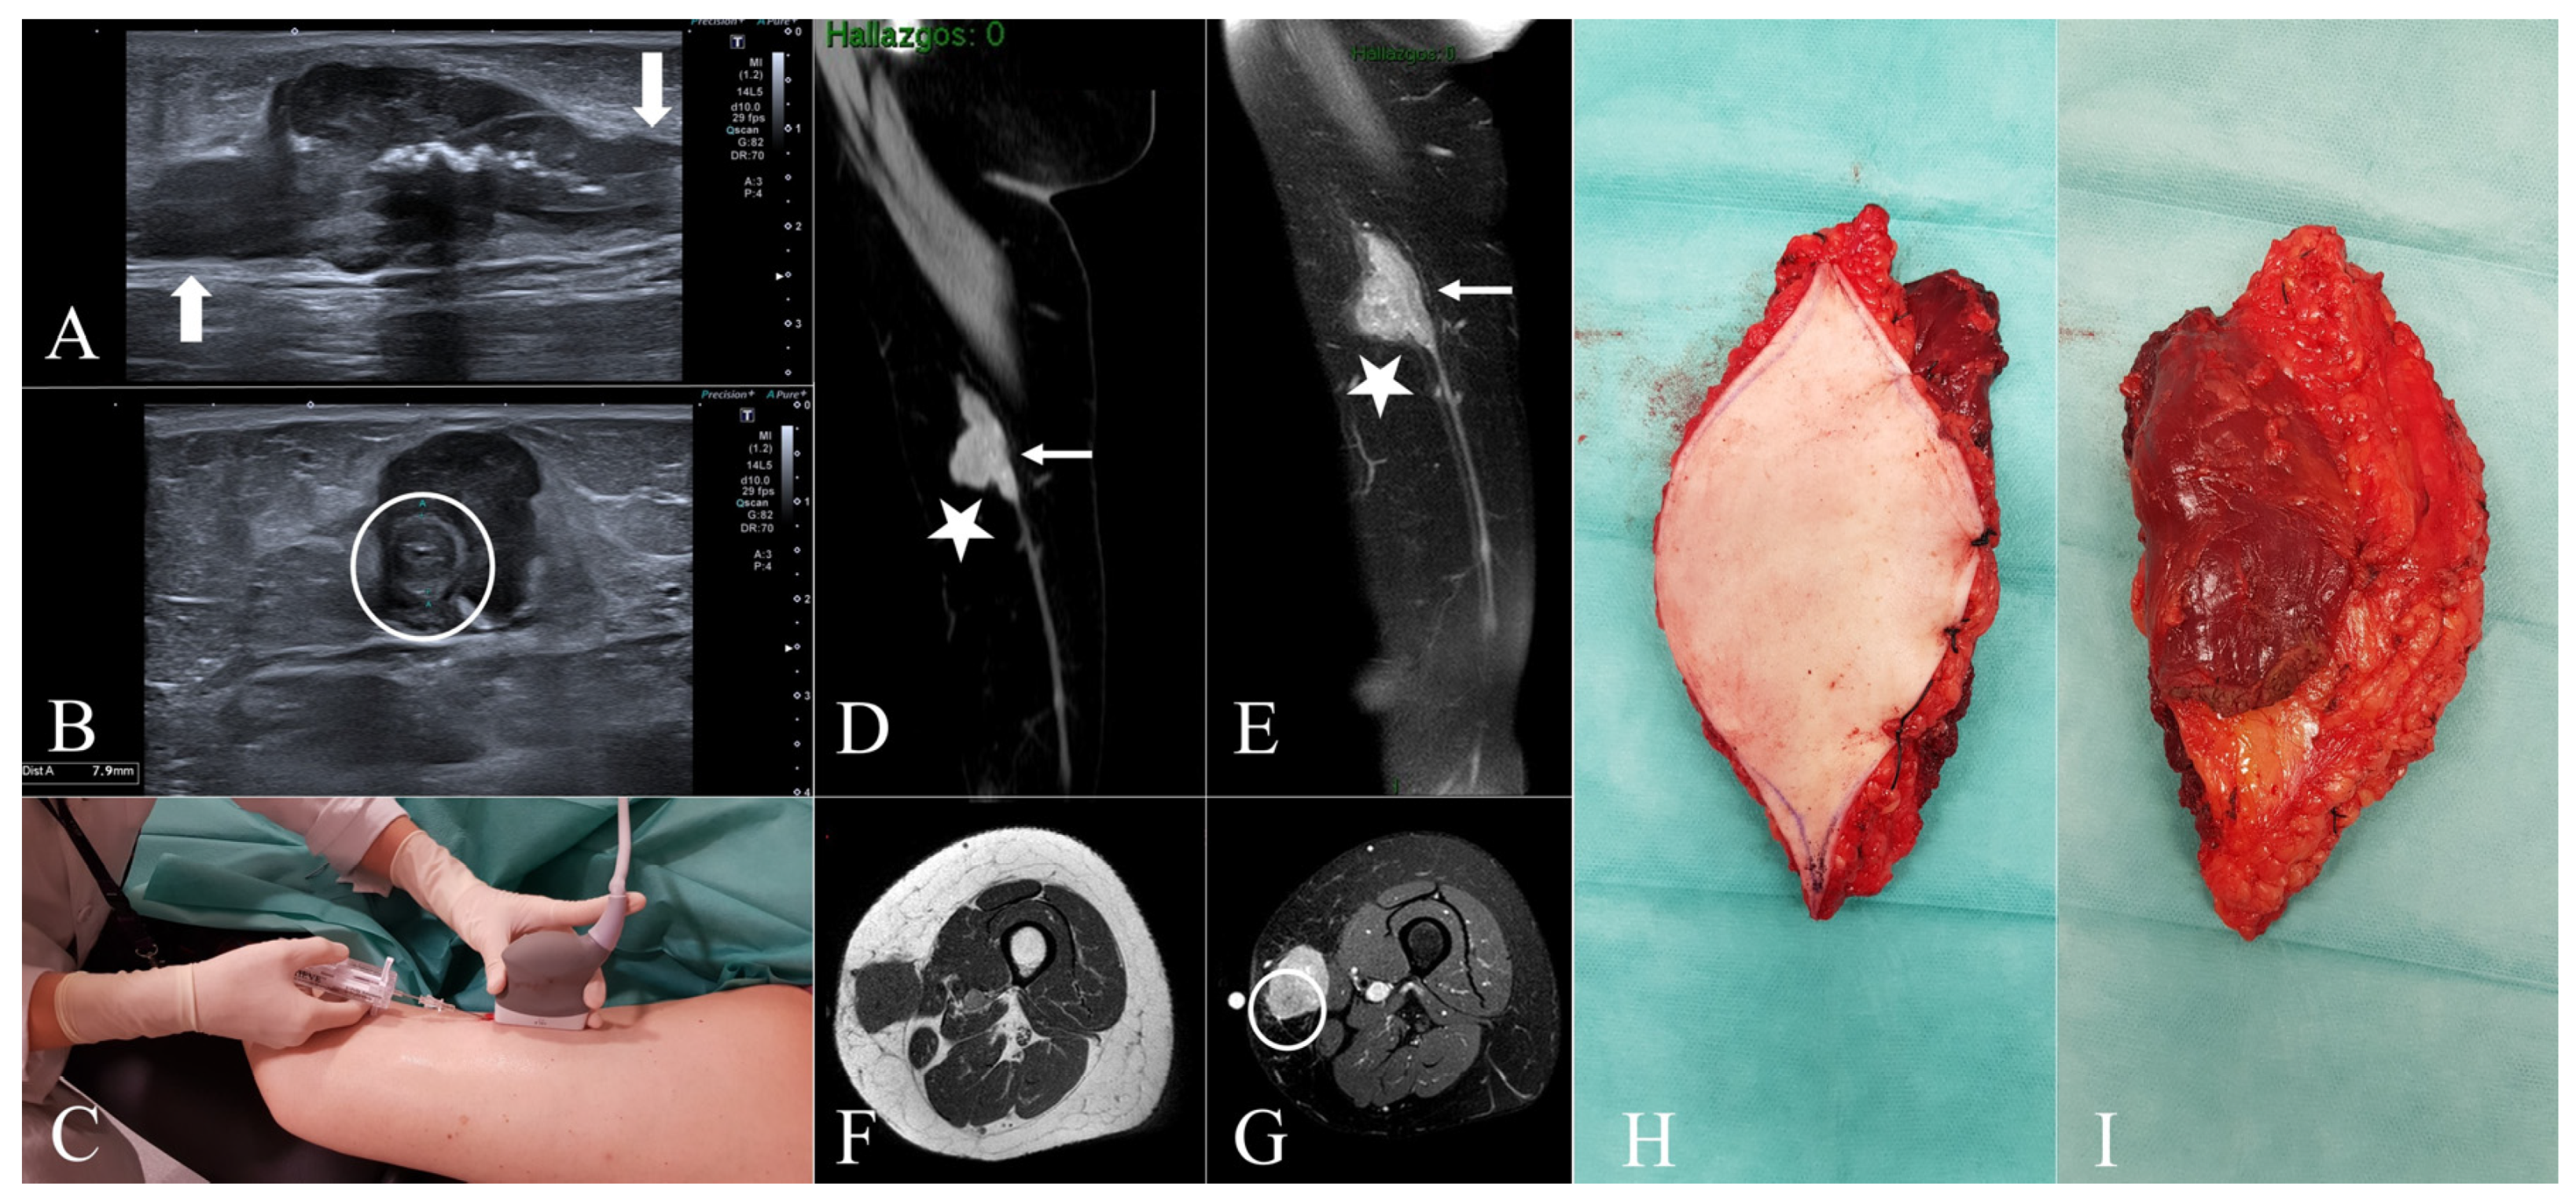

Figure 1.

Case 2. (A,B) = Ultrasound images show a well-defined solid subcutaneous soft tissue mass. The tubular structures on both ends (A) correspond with the great saphenous vein (white arrows). Note the mural thickening of the great saphenous vein (B), which is encased by the mass (white circle). (C) = Ultrasound-guided core needle biopsy. The biopsy should be planned so that the biopsy tract can be safely removed at the time of definitive surgery. (D,E) = Sagittal post-contrast CT and sagittal post-contrast T1W fat-suppressed images reveal mural thickening of a segment of the great saphenous vein (white arrows) and a polylobate soft tissue saphenous-dependent mass (white stars). (F) = Axial T1W images exhibit a well-circumscribed, isointense to muscle, and subcutaneous soft tissue mass. (G) = DP fat-suppressed axial image shows the hyperintensity of the mass and its relationship with the great saphenous vein (white circle), well correlated with transverse grayscale US (B). (H) = Superficial side of the specimen, including a large segment of skin. (I) = Deep side of the specimen, including the fascia and a muscular cuff to ensure a wide resection margin. Note the inclination of the biopsy needle so as not to cross the fascia and avoid contamination of healthy deep planes of the thigh. Also note the peripheral sealing of the specimen by means of stitches between the skin and the fascia (H).